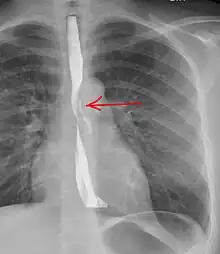

Upright chest radiography showing mediastinal air adjacent to the aorta and tracking cephalad adjacent to the left common carotid artery. This patient presented to the Emergency department with severe chest pain after eating.